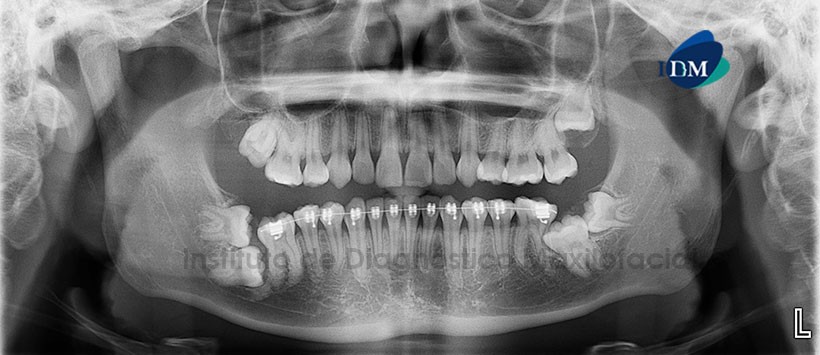

A la evaluación de la radiografía panorámica (Figura 1) se aprecia: Pieza 1.7 en posición buco palatina; Pieza 3.8 en posición horizontal e impactada contra la superficie distal de la corona de la pieza 3.7; así mismo se observa a la pieza 3.7 en posición mesioangular e impactada contra la superficie cervico-distal de la pieza 3.6, aparentemente ocasionando la reabsorción radicular de ésta última; Por otro lado se observa la superposición de los ápices sobre el conducto dentario inferior. Pieza 4.7 en posición horizontal e impactada sobre la superficie distal-radicular de la pieza 4.6; con el segmento radicular superpuesto sobre el conducto dentario inferior, así mismo se aprecia a la pieza 4.8 en posición horizontal y en posición cefálica con respecto a la pieza 4.7. Se aprecia, además aparatología fija para ortodoncia en las piezas inferiores. Para una mejor evaluación de la posición de las piezas impactadas y los efectos sobre estructuras adyacentes que puedan haber ocasionado, se decide realizar una ampliación con la tomografía volumétrica (CBCT).